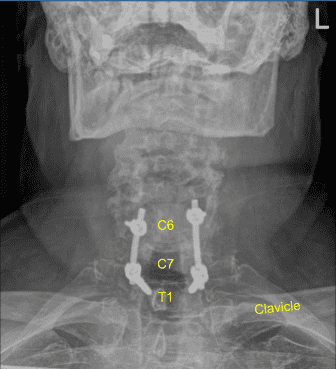

Se utilizó un marco estereotáctico guiado por imagen con técnicas de neuronavegación para colocar la instrumentación. Colocamos tornillos pediculares bilaterales T1 y decorticamos con canulación eléctrica de alta velocidad con el localizador pedicular de mano, palpando para detectar brechas, midiendo las profundidades, subroscando 11 mm y colocando tornillos pediculares de titanio de 30 mm x 5,0 mm bilateralmente sin dificultad.

Los potenciales evocados motores se comprobaban periódicamente y eran estables. A continuación, cenulamos las masas laterales bilaterales de C5 y C6 utilizando técnicas de navegación, decorticando con un taladro eléctrico de alta velocidad, canulando con una guía de perforación de 12 mm y un taladro eléctrico de mano, palpando en busca de brechas, y rellenando el agujero con Surgiflo.

A continuación, realizamos laminectomías C6, C7 y T1 perforando canaletas bilaterales bajo riego estéril continuo y resecando en bloque la lámina C6 y C7 con el rongeur de Leksell. Luego resecamos hueso residual y ligamento hipertrófico flavo con varios rongeurs de Kerrison protegiendo cuidadosamente la duramadremadre.

A continuación, colocamos tornillos bilaterales de masa lateral en C6. Al inspeccionar la deformidad de la columna, se decidió no colocar los tornillos de masa lateral C5 debido a la deformidad cifótica y la dificultad para colocar las varillas.

Así que luego decoricamos las articulaciones en C6-C7 y C7-T1 y los procesos transversales bilaterales T1 con un taladro eléctrico de alta velocidad para la artrodesis. El autoinjerto resecado fue fragmentado. Se colocaron varillas de titanio precortadas y predelineadas sobre los tulipanes desde C6 hasta T1, se aseguraron con tapones de bloqueo y luego se apretaron finalmente con un dispositivo de par y antitorque.